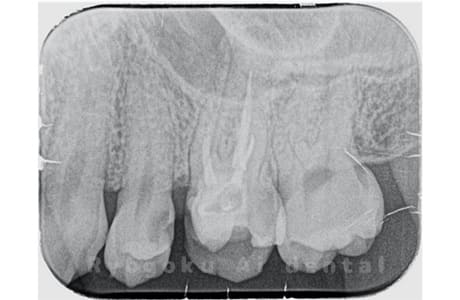

Case06

-

- 原因

- 慢性根尖性歯周炎

- 治療期間

- 2ヶ月

- 治療内容

- マイクロエンド

- 治療費用

- 121,000円

他院で治療終了で次回から被せ物の型取りを行うと説明された患者さんです。まだ痛みが残っていたためセカンドオピニオンでご来院してくださりました。再度根管治療を行い、痛みを完全に消失したケースです。

<リスク・副作用>

術後は痛み、腫れ、痺れなどの副作用が生じる場合があります。症状が再発する可能性があります。